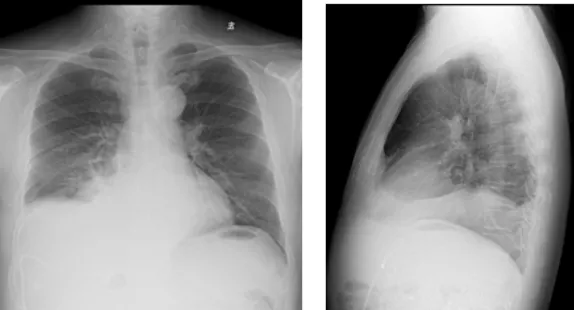

影像學檢查結果

右肺炎癥不能排除,請結合臨床。右側少量胸腔積液

右側胸腔積液細胞學檢查結果